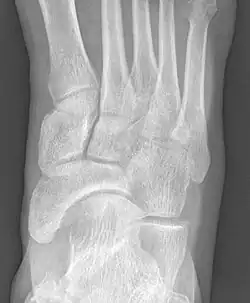

Radiographie du pied montrant un os naviculaire accessoire

Les radiographies sont généralement commandées pour confirmer le diagnostic. S'il y a une douleur ou une inflammation en cours, une IRM ou d'autres tests d'imagerie avancés peuvent être utilisés pour évaluer davantage la condition.

Images radiologiques